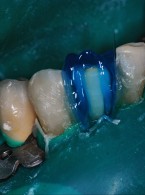

Pokrycie mnogich recesji dziąsłowych

metodą płata przesuniętego dokoronowo z wykorzystaniem przeszczepu podnabłonkowej tkanki łącznej i kolagenowego materiału ksenogennego po wcześniejszej rekonstrukcji połączenia szkliwno-cementowego - opis przypadku